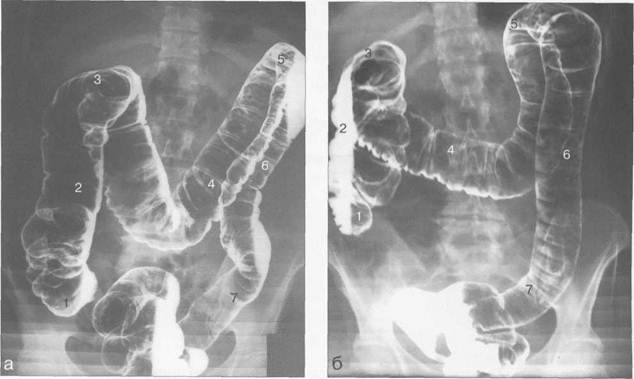

Рис. 11.37. Ирригоскопия. Первично-двойное контрастирование.

а — латерограмма в положении больного лежа на левом боку;

б — латерограмма в положении больного лежа на правом боку; в — рентгенограмма, сделанная в вертикальном положении больного. 1 — слепая кишка; 2 — восходящая ободочная кишка; 3 — печеночный изгиб; 4 — поперечная ободочная кишка; 5 — селезеночный изгиб; 6 — нисходящая ободочная кишка; 7 — сигмовидная кишка.